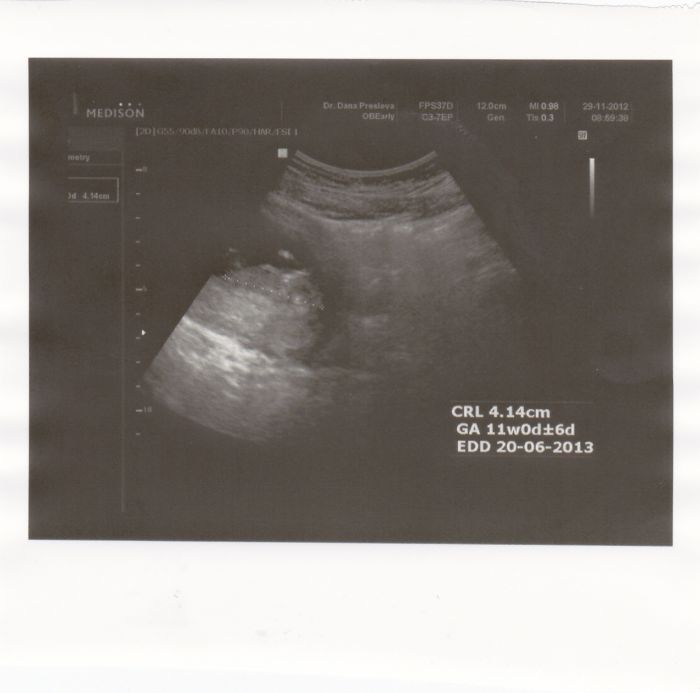

. Dneska jsme byli na ultrazvuku a opět ze mě spadl kámen ze srdce, že je vše v pořádku. Brali mi krev do třech zkumavek a mám zavolat za týden co a jak dá. Dávám sem i fotku našeho prťouska

Tak naše miminko měří 6.1cm zhruba bylo pěkně aktivní a nechtělo se ukázat z profilu vůbec :-D pořád ukazovalo zádíčka a nakonec se schoulilo i do klubíčka :D ale ukázalo nám jak umí krásně kopkat nožičkama :-) jinak jsme 12+4 a termín porodu podle MS i UTZ máme stejný 9.6 :D :-) Na downa to nevypadaá všechno máme v normě :-) na odběry jdeme 17.12. a poradnu máme 3.1. tam si budu platit pro mou jistotu utz a 24.1. máme velký utz :-)